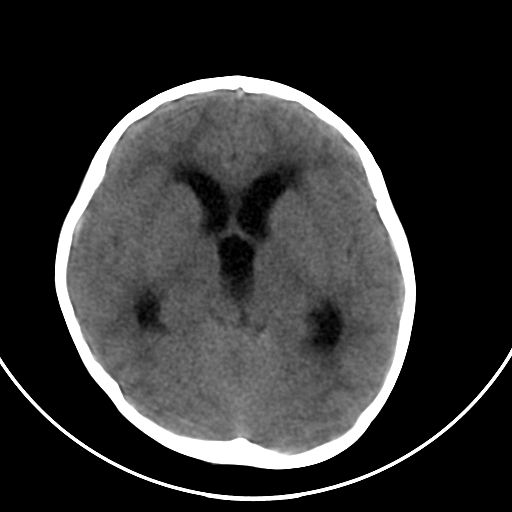

以下是引用zjzjr在2008-7-27 9:56:00的发言:[br]考虑髓母细胞瘤伴梗阻性脑积水.建议增强或mri

以下是引用子十在2008-7-27 9:53:00的发言:[br]考虑髓母细胞瘤